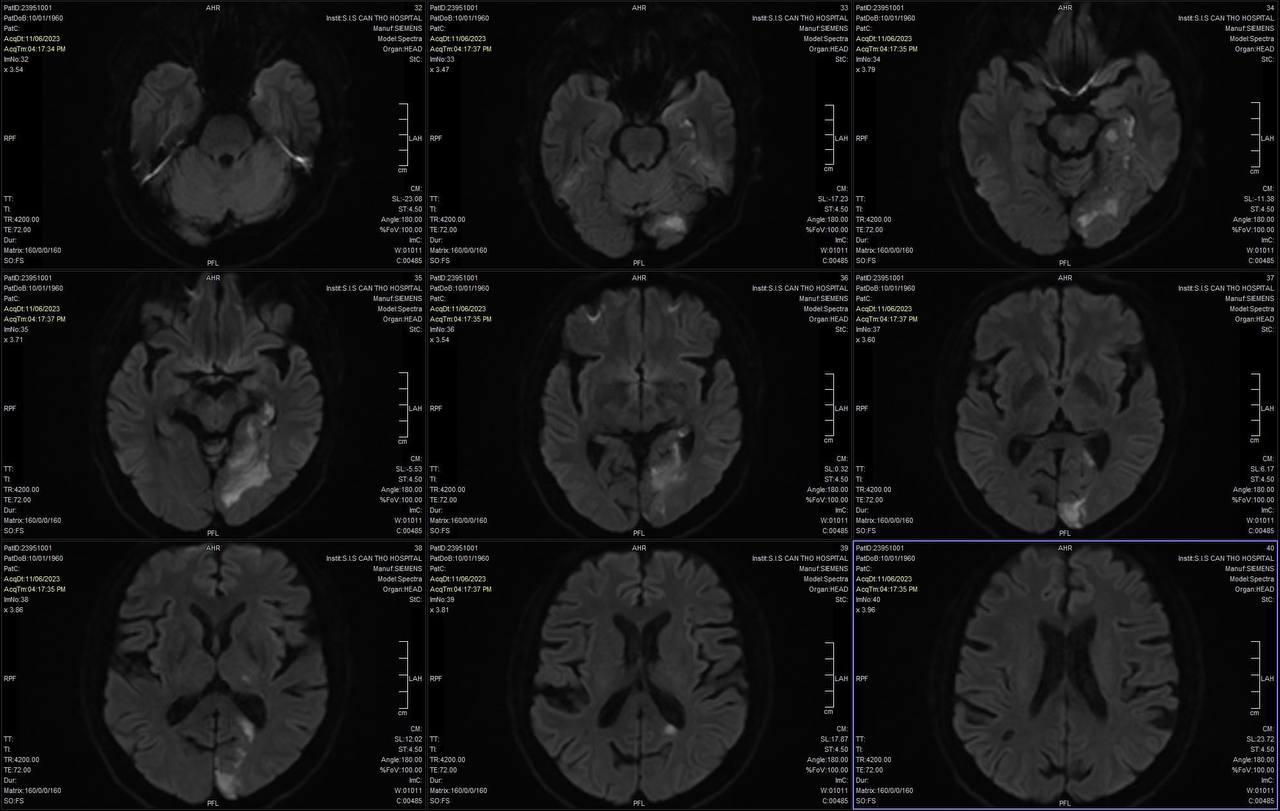

Ngày 10/11/2023, Bệnh viện Đa khoa (BVĐK) tỉnh Phú Thọ tổ chức Hội thảo “Cập nhật can thiệp lấy huyết khối cơ học trong đột quỵ nhồi máu não cấp” với sự tham gia của những chuyên gia, bác sĩ hàng đầu hoạt động trong lĩnh vực can thiệp mạch máu.

Ngày 2/11, trong đêm các bác sĩ Bệnh viện Đà Nẵng đã hội chẩn khẩn với các chuyên gia đột quỵ đầu ngành tại TPHCM để cứu sống bé trai 10 tuổi bị đột quỵ não hiếm gặp bằng thuốc tiêu sợi huyết.